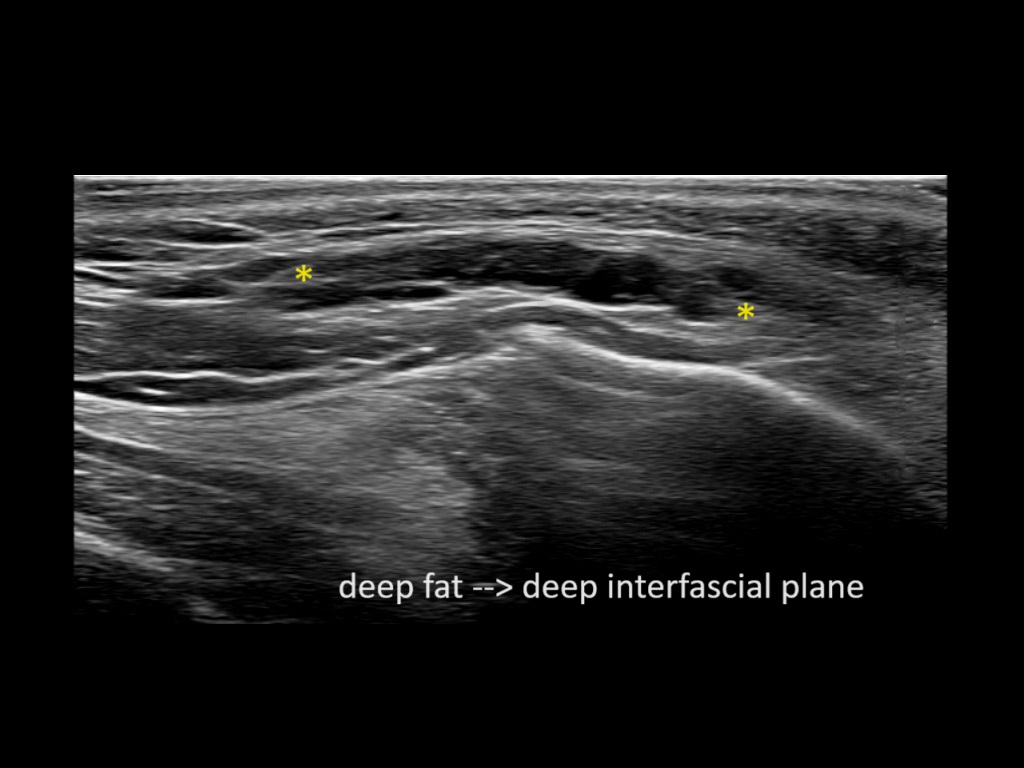

Filler behavior - Temple zygoma US

Study the first image to recognize the different layers. If you are sure about the layers, swipe to the second image to view the answer (if applicable).

Hover over an image to view the secondary image or click on the image title for more information.